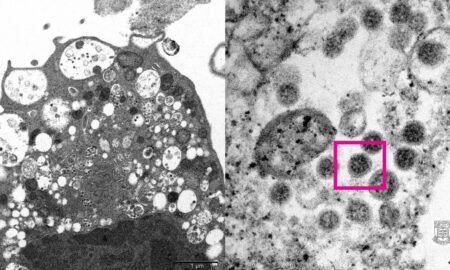

A Agência Nacional de Vigilância Sanitária (Anvisa) divulgou esta semana o que se sabe, até o momento, sobre a variante Ômicron. As...